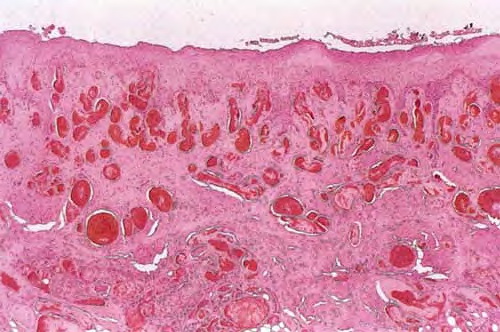

Gangrene = الموات